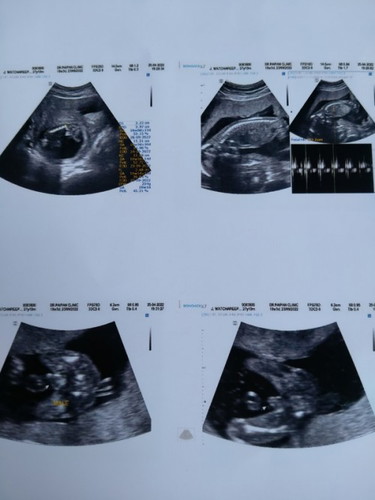

คุณหมอบอกว่าหนูเป็นผู้ชายแต่ยังไม่บอกว่าชัวร์100% แม่ๆคนไหนดูออกไหมค้ะว่าเป็นเพศชายหรือเพศหญิง#ขอบคุณล่วงหน้านะคะ #ขอบคุณสำหรับคำตอบค่ะ

แม่ๆช่วยดูให้บ้านนี้ด้วยได้มั้ยคะ 🥰 ตอนแรกที่ซาวด์เป็นเรียบๆคุณหมอบอกน่าจะผู้หญิง พอขยับๆไปมาก็เป็นแบบนี้ค่ะ คุณแม่อยากรู้มากว่าเป็นหญิงหรือชาย ช่วยดูให้ด้วยได้มั้ยคะ

ฝากแม่ๆๆช่วยดูด้วยคะชายรือหญิงแต่ลุงหมอบอกน้องเป็นผู้ชายแต่ไม่แน่ใจคะ

กี่เดือนแล้วค่ะ ภาพ ลองสุดท้าย กับภาพสุดท้าย ชัดมากเลยค่ะ เพศชายค่ะ

ซาวด์ตอน 18 สัปดาห์แล้วค่ะ

น่าจะชายชัวร์นะคะ ดูจากจุ๊ดจู๋ที่โผล่ออกมา ภาพล่างขวาค่ะ

ภาพสุดท้าย เท่าที่ดูเป็น ผช นะคะ เห็นจุ๊มุ๊ ชัดเลย 😁😁

ลูกชายค่ะ คล้ายๆกันเลย ภาพสุดท้ายชัดเจนมาก